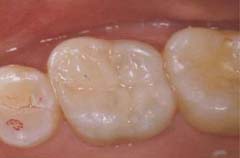

■異物の除去■

施術前

異物

施術後

「施術前」の写真は、他院から紹介で受診された患者さんのものです。治療中には不測の事態が起きることがあります。

写真には治療用の器具が写っています。

折れた器具を技術を駆使して取り去り、通常通り根を薬で詰めて治療は完了します。